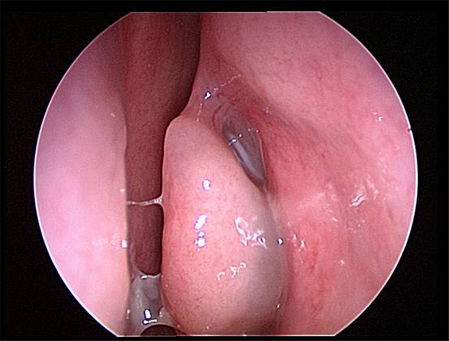

აუცილებელია ცხვირის ღრუს შემოწმება ლორწოვანი გარსის ერითემის ან ჩირქოვანი გამონადენის არსებობაზე. ოპტიმალური შემოწმების ჩატარება შესაძლებელია შეშუპების საწინააღმდეგო სპრეის ლოკალური დატანების შემდეგ.[17] როგორც ოტოსკოპი, ისე ნაზალური სარკე და რეფლექტორული განათება შეიძლება იყოს გამოყენებული. ცალმხრივი ჩირქოვანი გამონადენი, ლორწოვანი გარსის შეშუპება ან ერითემა, აგრეთვე სახის არეში მტკივნეულობა მიანიშნებს ბაქტერიული სინუსიტის არსებობაზე. არაჩირქოვანი გამონადენი საფიქრებელს ხდის ვირუსული ან ალერგიული ანთების არსებობას. იმის გათვალისწინებით, რომ ნაზალური გასინჯვა შესაძლოა იყოს გაძნელებული, ან ავლენდეს მხოლოდ არა-სპეციფიურ ნიშნებს, ცალკეული პაციენტებისთვის რეკომენდებულია ნაზალური ენდოსკოპიის ჩატარება, კერძოდ, ემპირიული ანტიბიოტიკოთერაპიის მიმართ რეფრაქტერული პაციენტებისთვის, როდესაც არსებობს ეჭვი ანტიბიოტიკებისადმი რეზისტენტობაზე, ან პაციენტი არის იმუნოკომპრომენტირებული.

ენდოსკოპია იძლევა ცხვირის ღრუს და სინუსების სადრენაჟე გზების საუკეთესო ვიზუალიზაციის საშუალებას. არსებობს ორი ტიპის ენდოსკოპი: რიგიდული და ელასტიური. რიგიდულ ნაზალურ ენდოსკოპს უკეთესი რეზოლუცია გააჩნია და მისი მართვა ცალი ხელით შეიძლება. ეს აადვილებს საჭიროების შემთხვევაში კულტურების მიღებას ცხვირის ღრუდან ან წიაღიდან. ელასტიური ნაზალური ენდოსკოპი პაციენტებისთვის უფრო კომფორტულია, მაგრამ მისი მართვა ორივე ხელის დახმარებით ხდება. არსებობს დრეკადი ცხვირის ენდოსკოპი, რომელსაც აქვს კულტურის შეგროვების არხი, მაგრამ უფრო დიდი და არასასიამოვნოა და მათი დამუშავებაც უფრო რთულია. ზოგადად, დრეკადი ენდოსკოპის გამოყენება უმჯობესია ბავშვთა ასაკში მისი კარგი ამტანობის გამო; თუმცა როგორც მოზრდილების, ისე ბავშვთა გამოსაკვლევად შესაძლებელია ორივე ტიპის ენდოსკოპის გამოყენება. არჩევანი დამოკიდებულია შემსრულებლიექიმის გამოცდილებაზე და შემთხვევათა უმეტესობაში იშეიძლება ჩაატაროს ყელ-ყურ-ცხვირის სპეციალისტმა.

[Figure caption and citation for the preceding image starts]: მარჯვენა შუა ნიჟარა და შუა გასასვლელი ხილვადია შეშუპების საწინააღმდეგო სპრეის დატანების შემდეგექ. Melissa Pynnonen-ის კოლექციიდან [Citation ends].